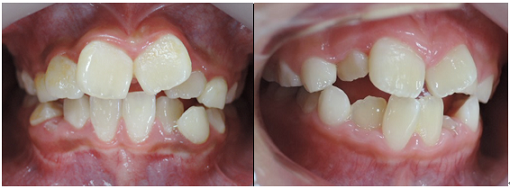

治療前 治療後

この様な歯並びの方はかなり見受けられるとと思われます。

当矯正歯科医院では、咬合バランスを改善する為には、

顎骨の拡大だけでは不十分と考ています。

その為、かみ合わせの高さなど立体的に改善していく事を心がけて日々治療しています。

今回も治療には、独自の方法とビムラー・t4k等を利用して改善しました。

今後、永久歯の歯並びは永久歯が萌えてから改善していく計画です。

顎骨のバランスは良好の為、永久歯を抜歯する必要は全くありません。